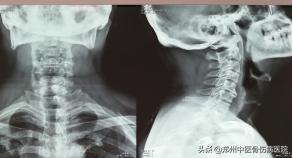

辅助检查:颈椎MRI:C3/4--C5/6椎间盘退行性病变